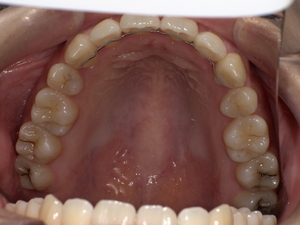

口の中に白っぽい「線状・網目状・斑点状」の病変が現れ、粘膜が硬く、時に痛みやヒリヒリ感、赤みを伴います。病変部がむずがゆい、物を噛むときに不快感がある、口内炎が繰り返すような感覚が現れる方も多いです。

特徴的な症状は以下の通り:

白く盛り上がった粘膜(網目状または板状)

赤みを伴う潰瘍状の病変

痛みや焼けるような違和感

唾液が増えたり、食事時にしみる感じ

これらが合わさることで生活の質に影響が出るケースもあります。

口の中のどこにできる?(舌・頬・歯茎など)

頬の内側:もっとも一般的。

舌の横や裏:白斑が見られやすいです。

歯茎や唇の裏:発生することもあり、視認しづらいため注意が必要。

口蓋(上顎内側):稀に見られる部位。